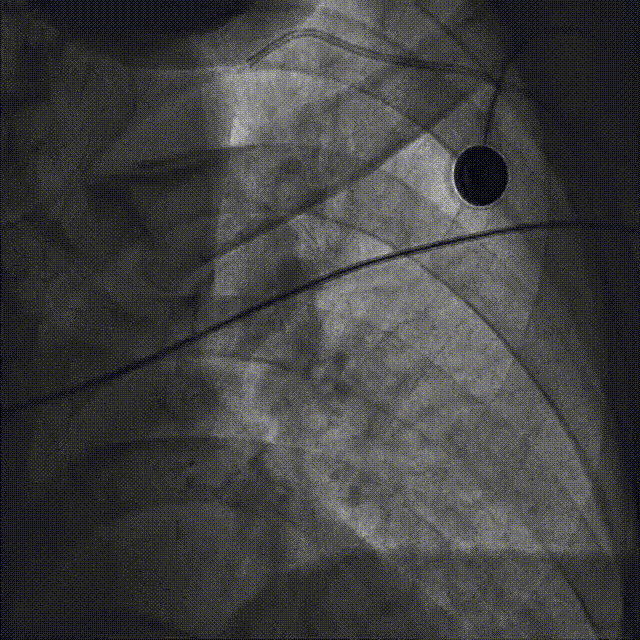

在微导管支撑下,Sion导丝无法经OM1心外膜侧枝逆向至LAD远段,改送Fielder XT-R导丝逆向至LAD远段。

HighTrack微导管跟进至闭塞病变远端,正向工作导丝做指引,应用Fielder XT-A导丝逆向通过闭塞段至LM内,反复尝试调整导丝未能进入正向指引导管。

此病例心外膜侧枝迂曲纤细,可见明显成角,故选择通过性好,远端外径1.5Fr的在HighTrack微导管;此外,对比间隔侧枝,心外膜侧枝缺乏心肌保护,往往存在更高的穿孔等并发症风险,因此头端纤薄柔软的HighTrack微导管尤其适用于此类病例。